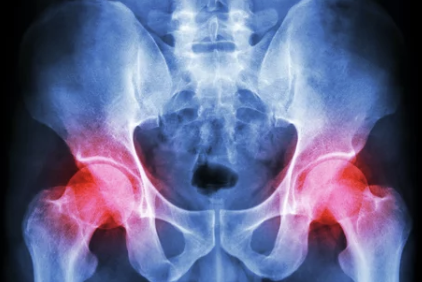

2) 관절염

- 퇴행성 관절염(골관절염): 연령 증가로 인해 고관절의 연골이 닳아 통증과 뻣뻣함이 발생.

- 류마티스 관절염: 면역체계 이상으로 인해 관절에 염증이 생기며, 고관절을 포함한 다발성 통증이 나타남.

- 강직성 척추염: 척추와 고관절 주변 관절에 염증이 생기며, 아침에 뻣뻣함과 통증이 심해짐.